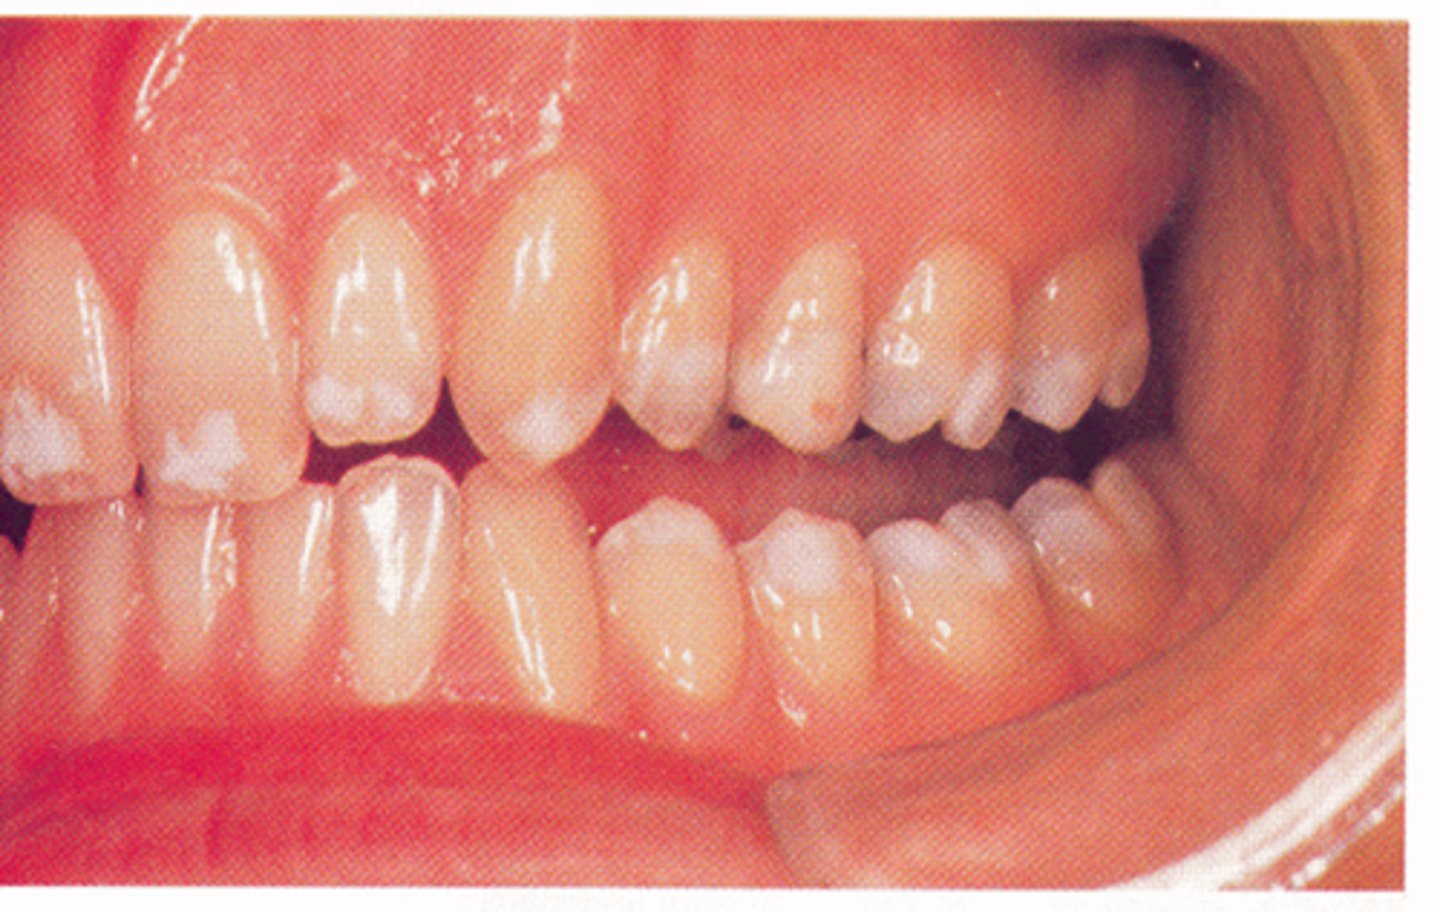

Type III: Hypomaturation amelogenesis imperfecta

1. Enamel is softer than normal

2. "Snowcapped"